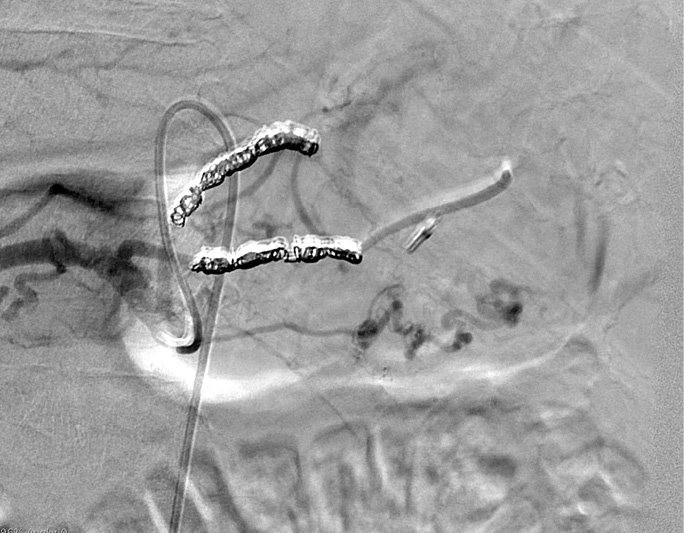

A 55-year-old male patient arrived at the Emergency Department of the Republican Vilnius University Hospital complaining of black stools and general weakness for only 1-day, tachycardia and low arterial blood pressure. UGIB was suspected. An extra esophagogastroduodenoscopy was performed. Arterial bleeding was observed from the posterior stomach wall in the border of the body/upper third of the stomach (Figures 1, 2). No pathological formations were visible in the mucosa. Dieulafoy’s lesion was suspected. The abdominal surgeon/endoscopist immediately started to stop the bleeding with adrenaline injection, but it was not enough. When we used endoscopic clip (Figures 3, 4). Bleeding was completely stopped. Patient’s condition was stabilized. But disease remained unknown. In order to reduce the risk of recurrent bleeding, we performed selective angiography of truncus coeliacus and embolization of the distal branches of arteria gastrica sinistra and some arteria lienalis branches, that feed formation through collateral blood flow (Figure 5). Large microspheres and pushing spirals were used for embolization (Figures 6, 7). The cause of bleeding still remained surely unknown. Now we suspected tumor. Only after by detailed strict anamnesis based on the patient’s life history, we conclude that the patient has a genetic disorder – Grönblad-Strandberg syndrome. According to our data, only four people suffer from this syndrome in Lithuania. Adjacent to this the patient had been operated for rectal cancer in the past, followed by ileostomy closure and abdominal wall hernioplasty for postoperative hernia. It is currently known that the patient has metastases in the liver and brain. The spread of cancer metastases, wide and severe comorbidities worsen the patient’s current condition, but despise these severe illnesses after proper and timely interventions, the patient lives without recurrent bleeding until now.

Figure 6. Transcatheter vascular embolization (partial)

Figure 7. Transcatheter vascular embolization (complete)